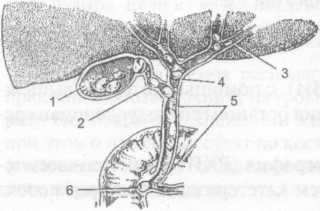

Анатомия и особенности Гартманова кармана желчного пузыря

/the-gallbladder-and-bile-ducts-in-situ-141483125-5a976f51fa6bcc0037583f66.jpg)

Раздел: Фотопанорама